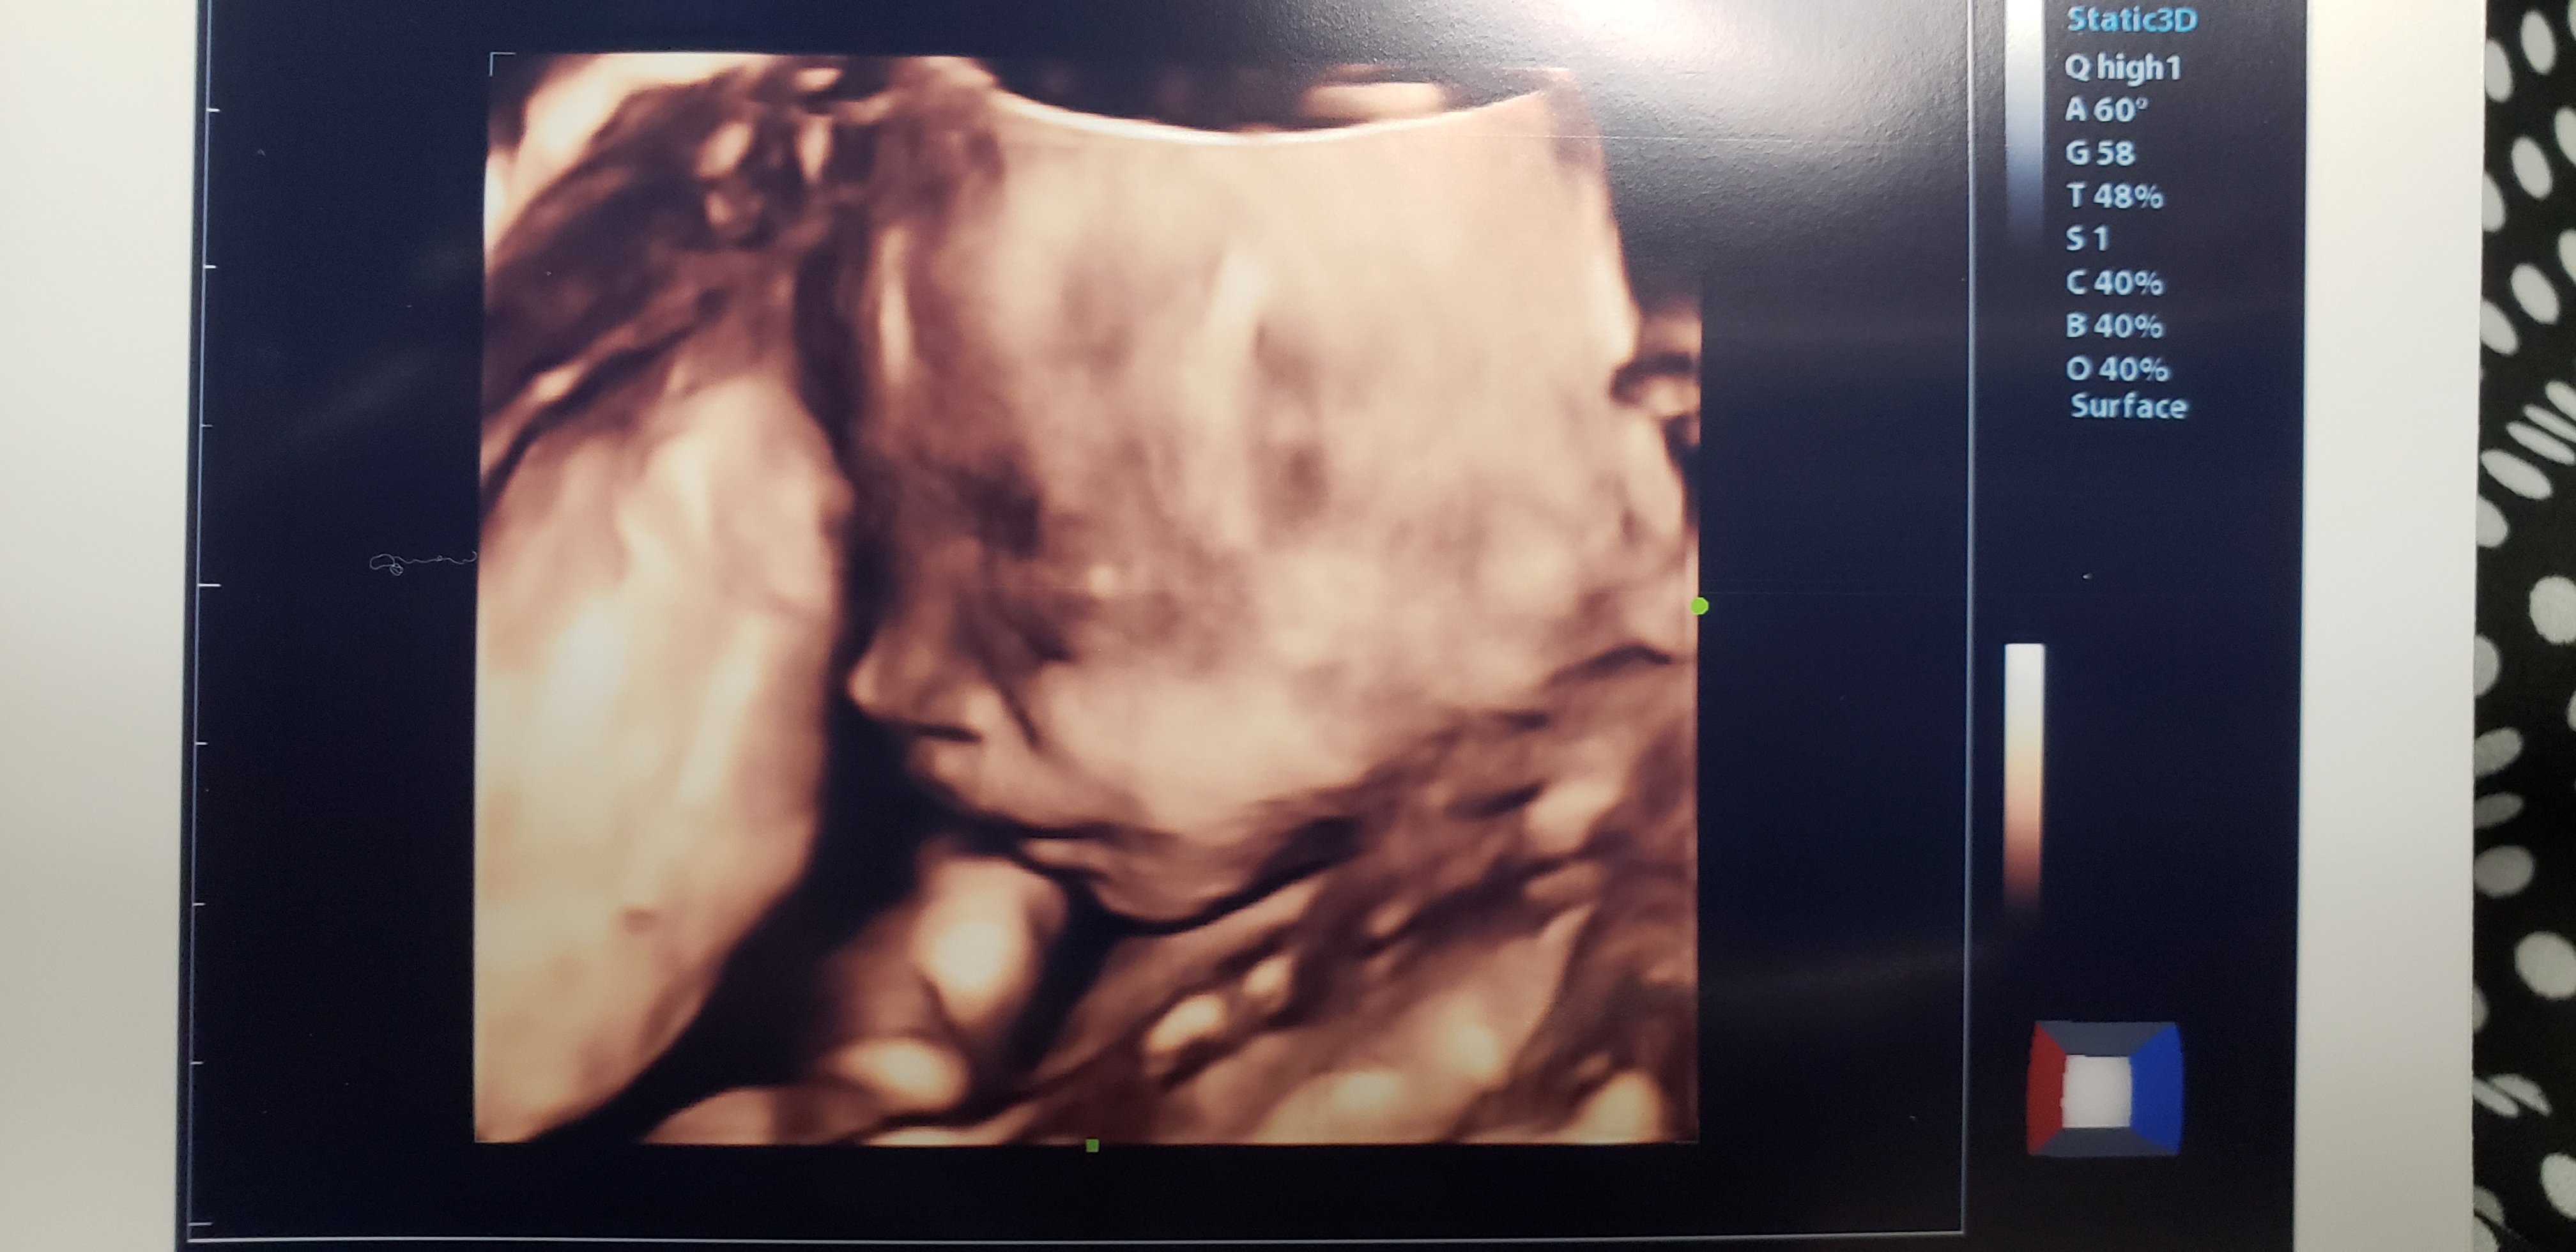

Evelyn grace. 20 weeks! So excited for our third baby girl

20 week ultrasound ❤️❤️